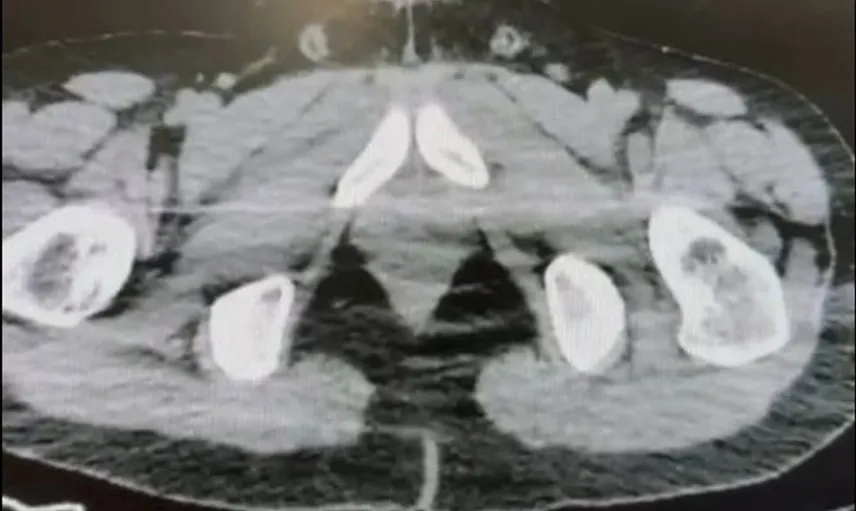

Ekiplerin sokak satıcılarına yönelik çalışmalarını yoğunlaştırması sonucu, şüpheliler S.B. ve O.R.'nin "yutma yöntemi" ile kente uyuşturucu madde sevk edeceği bilgisi üzerine operasyon düzenlendi. Şüphelilerin ikametlerinde ve araçlarında aramalar yapıldı.

Aramalarda; 101 kapsül halinde 722 gram uyuşturucu madde, 1 adet hassas terazi, yutma yönteminde kullanılan muhtelif materyaller ile uyuşturucu ticaretinden elde edildiği belirtilen 20 bin 210 TL, bin 320 euro ve 10 ABD doları ele geçirildi.